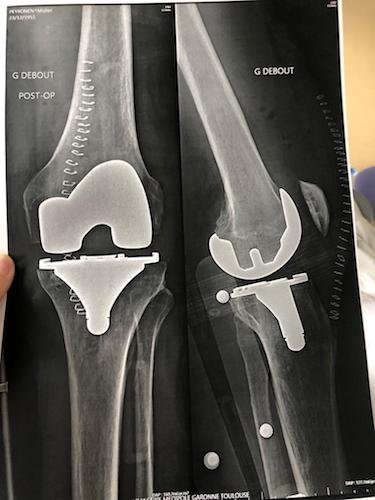

Rassurez-vous, son genou tout neuf en titane à tenu ; mais je ne vous dis pas l’état du pare choc de l’auto !

- Le genou de Michel.jpeg (31.82 Kio) Vu 5143 fois

Le genou de Michel